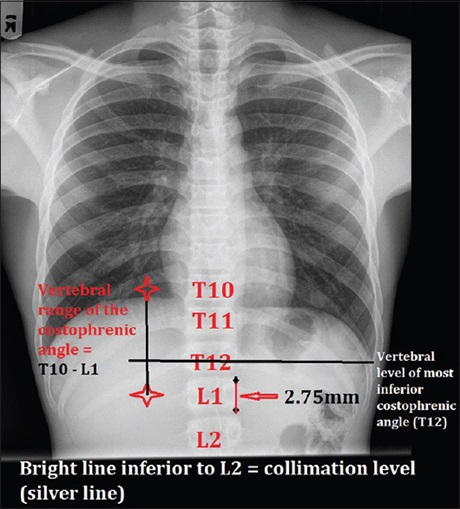

Methodology: The work was designed to radiographically test the hypothesis that the umbilicus which is an external landmark that can both be seen and felt is the most appropriate anatomical landmark to consider as inferior collimation border in chest examinations. Computed tomography was used to confirm L3 and L4 as the corresponding dorsal bony landmark of the lower costal margin and umbilicus, respectively. Participants were radiographically examined with a collimation at an axial plane, 5.5 cm superior to the umbilicus. The maximum distance between the most inferior costophrenic angle and the collimation border on the radiograph was also determined. Data were manually tabulated.

Results: The radiographs of 222 male and 216 female (n = 438) individuals were analyzed. 5.5 cm collimation coincided with L2 to T11 levels with 61% of individuals having costophrenic angles at T12 while only 3.7% had it high up at T10. No incidence of costophrenic angle cutoff was observed.

Conclusion: Inferior collimation for chest X-ray in adults is adequate at an axial plane 5.5 cm superior to the umbilicus along the xipho-umbilical line on a patient at full inspiration. This point is a constant landmark when compared to X-ray beam centering point for chest radiography in the same patient which will be variable.